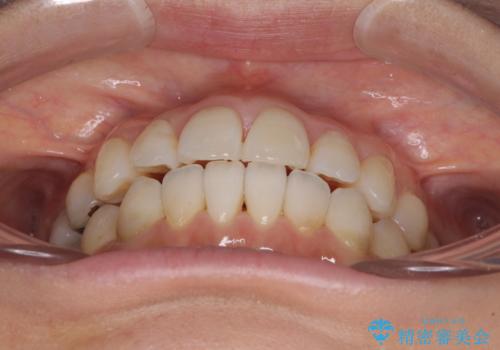

インビザライン・ライトによる矯正治療であったので、時間をかけずに治療を終えることができました。

口を開ける度に目立っていた銀歯もセラミックで自然な口元の印象となりました。